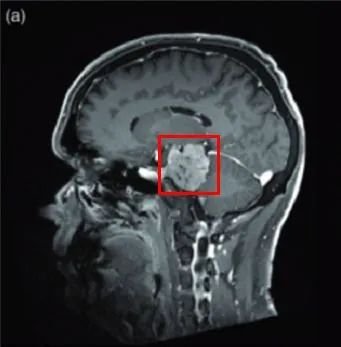

2005年,75岁的法国女士因右侧海绵窦脑膜瘤进行了一次开颅手术。2016年,左侧视力进行性下降,检查视力结果左侧视力4.6(右侧5.0),左侧视神经管内侧病变均匀增强,还报告翼点空化是由颞肌萎缩引起的。诊断确定脑膜瘤位于视神经管的中下侧(图1),导致了视力严重恶化。

手术方式:内镜辅助下右额下入路肿瘤全切术(图2)

图2:手术入路,右额下入路(入路方向大致如图)

手术过程:一阶段,通过钻取蝶缘和内侧视神经管进行视神经减压术,为后续手术做准备。二阶段经,经额下入路(图3)为对侧交叉沟和视神经提供绝佳手术通道,可以保障顺利切除肿瘤(图4)

·肿瘤完全切除(辛普森II)(图5)

图5:术前及术后磁共振成像。术前preop(A)和术后Postop(C)显示肿瘤完全切除,视神经保留完好,无脑水肿、出血等。